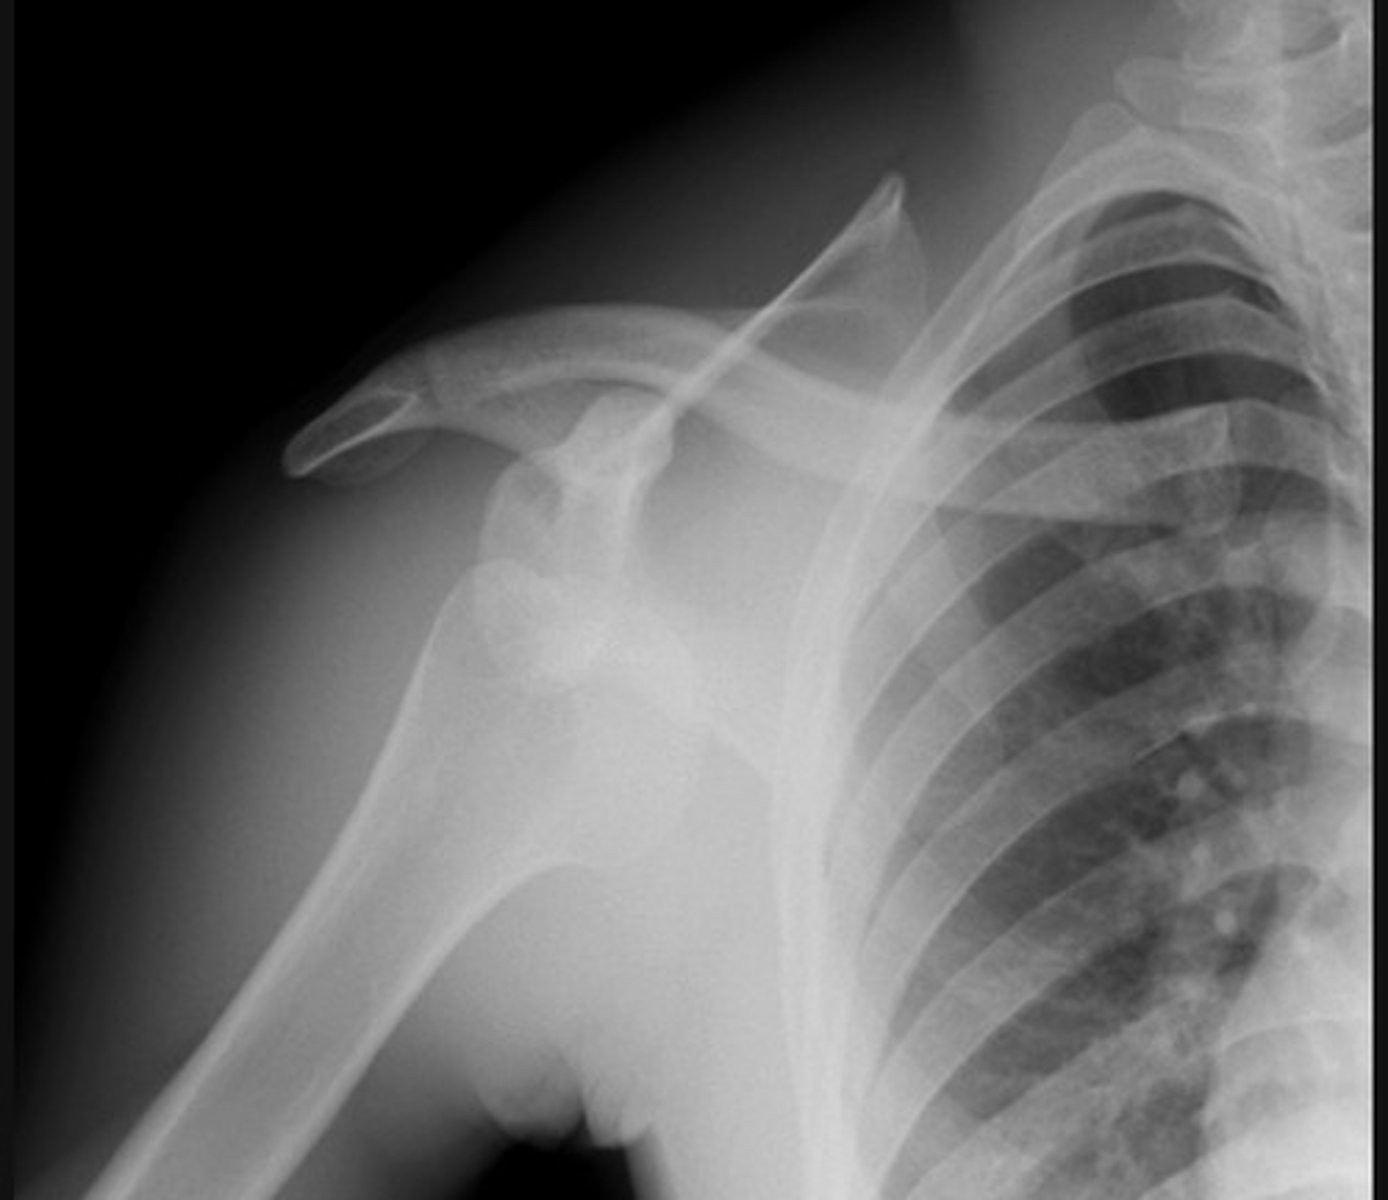

Posterior dislocation, 'lightbulb sign'